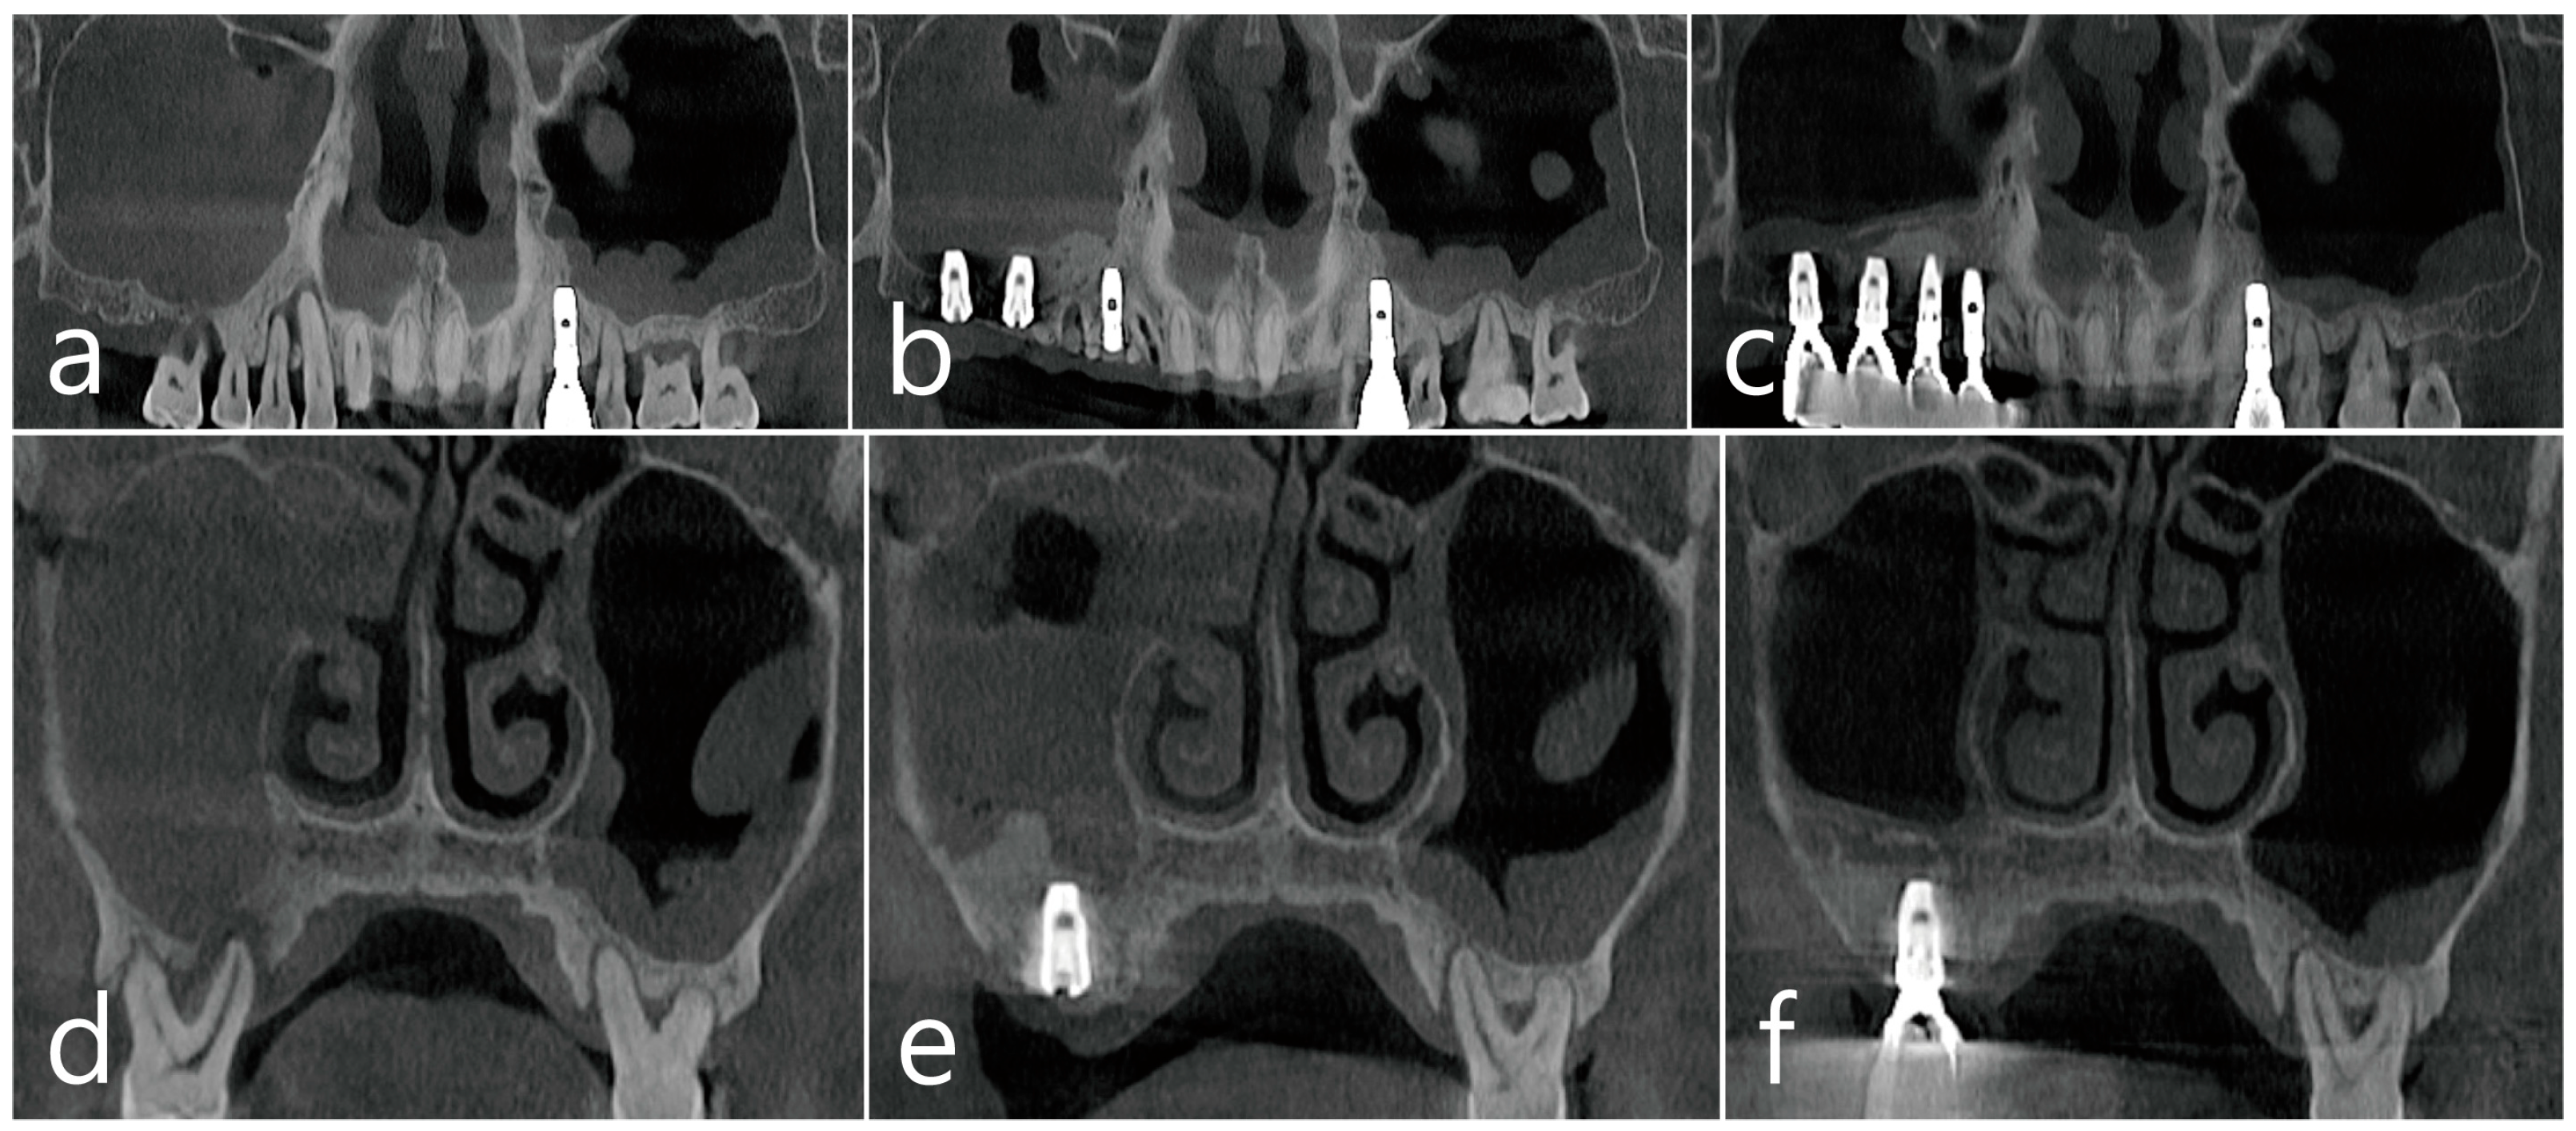

2.1. Case 1

2.2. Case 2